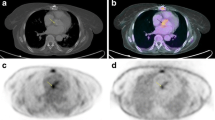

A subvolume containing the prosthetic valve is segmented to adequately visualize the valvular region and to exclude close malignant or suspicious pathological masses or nodules that might interfere with the analysis. Once the subvolume is generated, the orientation of the image plane is necessary to precisely visualize the valvular plane. The correct orientation is achieved when the coronal plane’s normal vector is aligned with the valve’s front-face normal vector, while the axial and sagittal image planes show the top and lateral views of the valve. Nevertheless, the orientation process may be heterogeneous between studies due to anatomical disparities of the patients (Fig. 1). Therefore, volume rotation may be required to ensure the correct visualization of the valvular plane. In preference to minimize the derived interpolation artifacts from rotation operations and to preserve original image features, a unique rotation is applied. By means of Euler’s theorem, the equivalent rotation angle and axis are calculated as from the history of rotations conducted by the user. This proceeding is applied on every step of the orientation process, so as the correction of the interpolation artifact is displayed in real time.

a [18F]FDG PET/CT image in coronal, axial and sagittal slices showing focal enhancement over the aortic prosthetic valve, difficult to objectify and localize in the visual analysis. b Prosthetic ring correct orientation and definition of the 90° segments. Counterclockwise definition of the 90° segments regarding to the maximum uptake focus, allocated in the center of the first segment

Once the definite valvular plane is defined, a three-dimensional toroid-shaped mask is generated to segment the metabolic activity of the prosthetic ring. Then, the quantitative parameters of metabolic activity, SUVmax and SUVmean, are extracted from both inner and outer sections of the toroid. Additionally, these quantitative metrics are computed of four 90º segments defining anterior, posterior, and lateral portions of the segmented valve. As mentioned, anatomical disparities between patients may result in different valve plane orientations so that the anterior, posterior, and lateral portions definition is not strictly adhered. However, to advantageously locate the anatomical reference points with respect the prosthetic valve, a maximum intensity projection image of the oriented CT volume is provided. Moreover, to increase the reproducibility and interpretation of the results, a criterion is followed, allocating the maximum uptake focus inside the first defined segment (Fig. 1). This means that the maximum uptake focus does not fall right in the space between two segments. In this manner, the focal nature of the uptake is preserved, adequately reflecting the heterogeneity between segments. The rest of the segments are then calculated regarding the first one, counterclockwise.